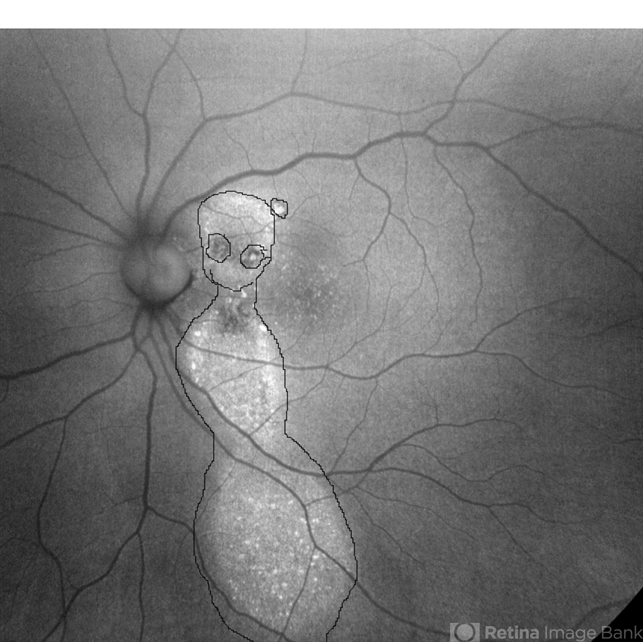

- Central Serous Chorioretinopathy (CSR), idiopathic central serous choroidopathy (ICSC), fundus autofluorescence (FAF), autofluorescence imaging

- 37-year male with chronic CSR